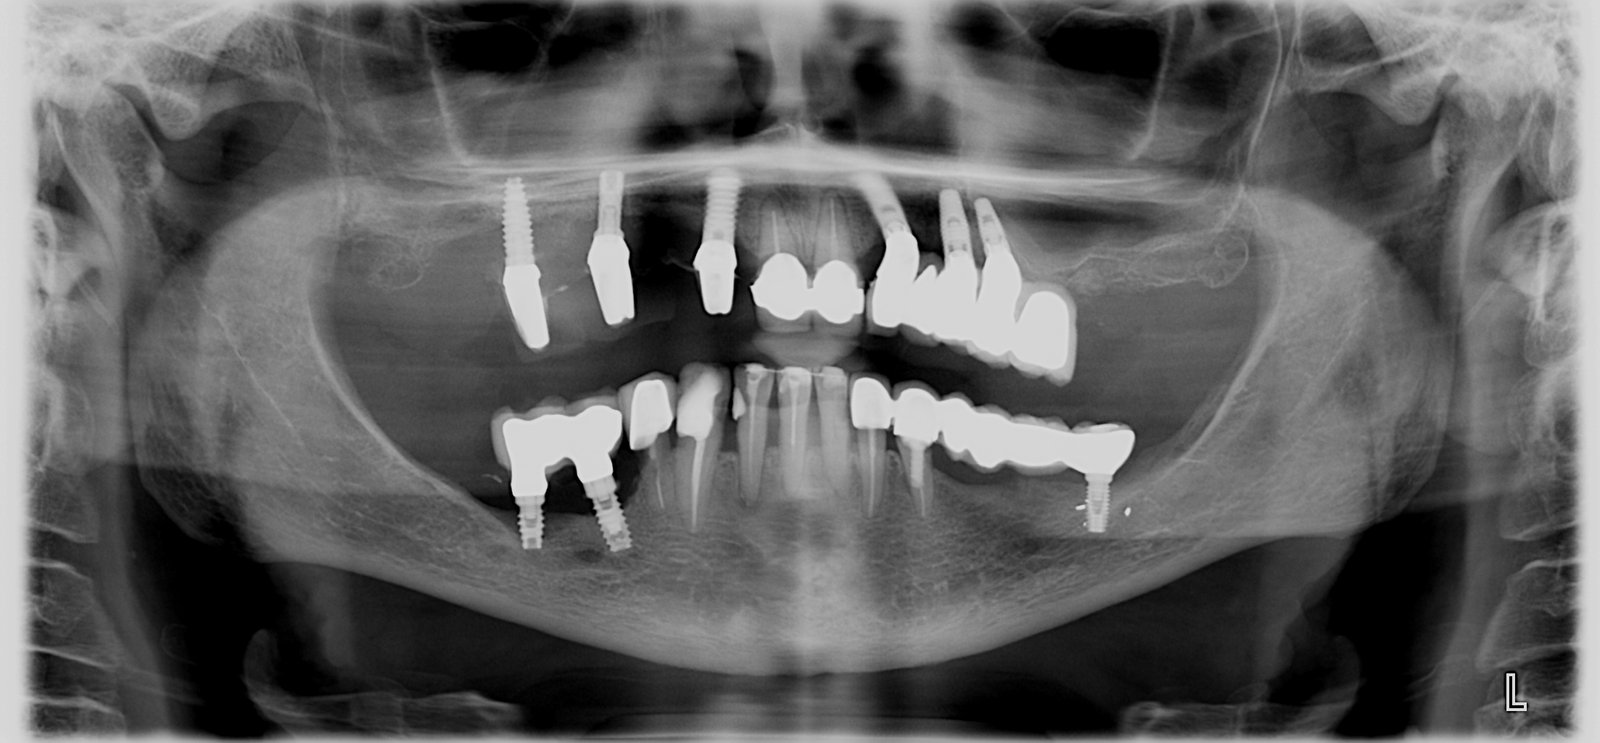

Indentificar implante distal

Hola! Necesitaría saber qué marca es el implante distal, con el pilar que sale en la foto. Compatibilidad para los aditamentos, etc. Y si me decís también que tipo de [...]

Buena tarde, me podran ayudar con la marca de este implante? ya intente compatibilidad con MIS, Neobiotech, Nobel y no fue compatible Gracias

Buenos dias , me pueden ayudar a saber que implante es? al parecer es de 5mm de diametro , tiene conexion interna de color verde, no tiene tapon de cierre [...]

Buenas tardes: me ha llegado este caso para cambiar corona, no sé qué implante es. Cuando retiro el transepitelial queda un aditamento de interfase que no se como retirar. Gracias

Hola compañeros, tengo esta paciente con implantes en posición 14 y 15 colocados hace alrededor de 20-30 años en Argentina. Tiene las coronas con la porcelana en malas condiciones y [...]

Lleva estos implantes de hace 5 años, en el tornillo de cierre pone R-2.7. Se los pusieron en Madrid en una policlínica. Gracias

Me gustaria conocer la marca y referencias de estos implantes colocados para en un principio rehabilitar un 36, fueron colocados en francia hace unos 6-7 años.nunca han sido rehabilitados. gracias!!

Buenas tardes, Solicito por favor, averiguar la marca del Implante en posición de la pieza 37. Muchas Gracias.

Buenas tardes, me gustaria saber la marca y demás informacion de implantes en posición 21-22 para realizar nuevas coronas metal cerámica. La conexión es interna la paciente no tiene posibilidad [...]